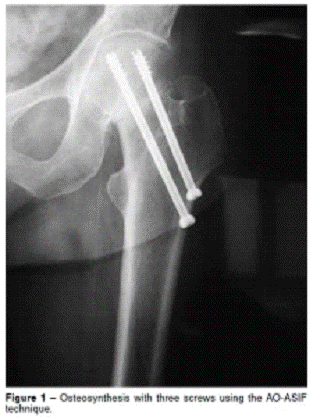

ПРИЛОЖЕНИЕ 21

Статический блокированный остеосинтез

представлен на рисунке 21

Рис.21. Статический блокированный остеосинтез